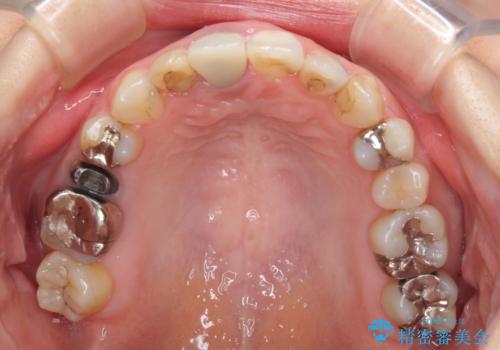

前歯のクロスバイトと治療が必要なむし歯 矯正とセラミックの総合歯科治療

前歯のクロスバイトはインビザラインで改善し、抜歯が必要な部分はインプラントを、その他むし歯が進行している歯はセラミッククラウンによる補綴治療することとしました。

仕事がお忙しく、インビザラインをあまりしっかりと使用できなかったようで、何とか長い期間をかけて歯列を整えることができました。

磨きにくく、何度もむし歯治療を繰り返していた前歯をスッキリと整えることができました。